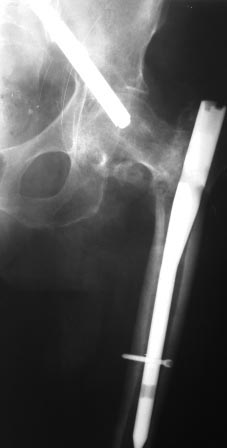

миграция винта

Доброе время суток коллеги. Прошу Вашей помощи, подскажите, как лучше удалить винт.

пациента по поводу вертельного перелома бедра оперирована 7 недель назад, в быту ходила с нагрузкой. около 2-х дней назад упала. На снимках вот такая картина. Сам ранее только читал, сейчас встретился воочию.